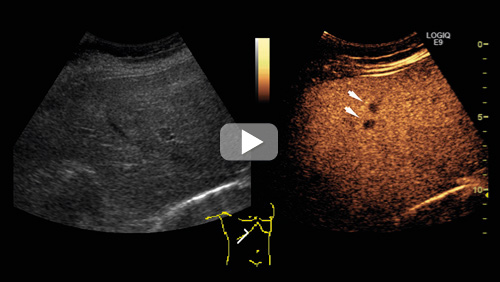

På bildet over til venstre vises et konvensjonelt ultralydbilde gjennom leveren, til høyre det korresponderende kontrastforsterkede bildet. Det kontrastforsterkede bildet er tatt i sen kontrastfase, og man kan se flere typiske metastaser som mørke flekker på lys bakgrunn (se video på nett for fremstilling av hele høyre leverlapp). Eksemplet viser en metastase fra tykktarmskreft. Det er betydelig lettere å identifisere metastasene på de kontrastforsterkede bildene.